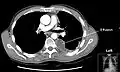

Chest computed tomography is more accurate for diagnosis and may be obtained to better characterize the presence, size, and characteristics of a pleural effusion. Lung ultrasound, nearly as accurate as CT and more accurate than chest X-ray, is increasingly being used at the point of care to diagnose pleural effusions, with the advantage that it is a safe, dynamic, and repeatable imaging modality.[17] To increase diagnostic accuracy of detection of pleural effusion sonographically, markers such as boomerang and VIP signs can be utilized.[18]

CT scan of the chest showing a left-sided pleural effusion. The fluid usually settles at the lowest space due to gravity; in this case, at the back because the patient is supine.- The lung expanding within an area of pleural effusion as seen by ultrasound